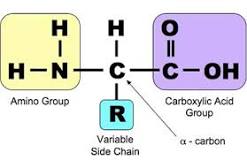

قیمت: 32٬000 تومان - دسته بندی فایل: پاورپوینتپاورپوینت شناسایی آمینواسیدها

فروش ویژه پاورپوینت حرفه ای شناسایی آمینواسیدهاباتخفیف استثنایی فقط54000هزارتومان تعداداسلاید.19اسلایدکامل